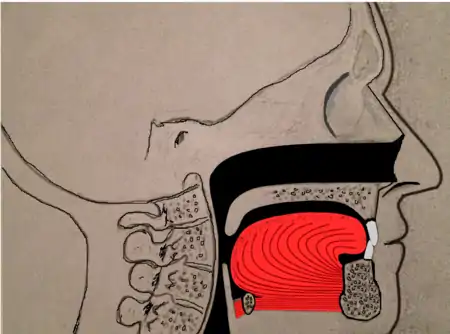

Genioglossus advancement

Genioglossus advancement (GA) also known as genial tubercle advancement (GTA), is a procedure that pulls the base of the tongue forward, usually to increase airway size due to deformity or a sleep breathing disorder. This procedure is frequently performed with either uvulopalatopharyngoplasty or maxillomandibular advancement surgeries.

Tongue muscles (genioglossus, geniohyoid and others) are attached to the lower jaw below the teeth. During a genioglossus advancement procedure, the surgeon cuts a small window or bone cut in the front part of the lower jaw (mandible) at the level of the geniotubercle where the genioglossus muscle attaches. This piece of bone, along with the attachment for the tongue (genial tubercle) is pulled forward and subsequently secured to the lower jaw, usually with a single screw or with a plate and screws.

This procedure is often combined with other surgeries such as uvulopalatopharyngoplasties or maxillomandibular advancement surgeries. It is rare to have this procedure performed as the only surgical treatment for sleep apnea, as obstruction in sleep apnea is most often at multiple levels (nose, palate, tongue, etc.).